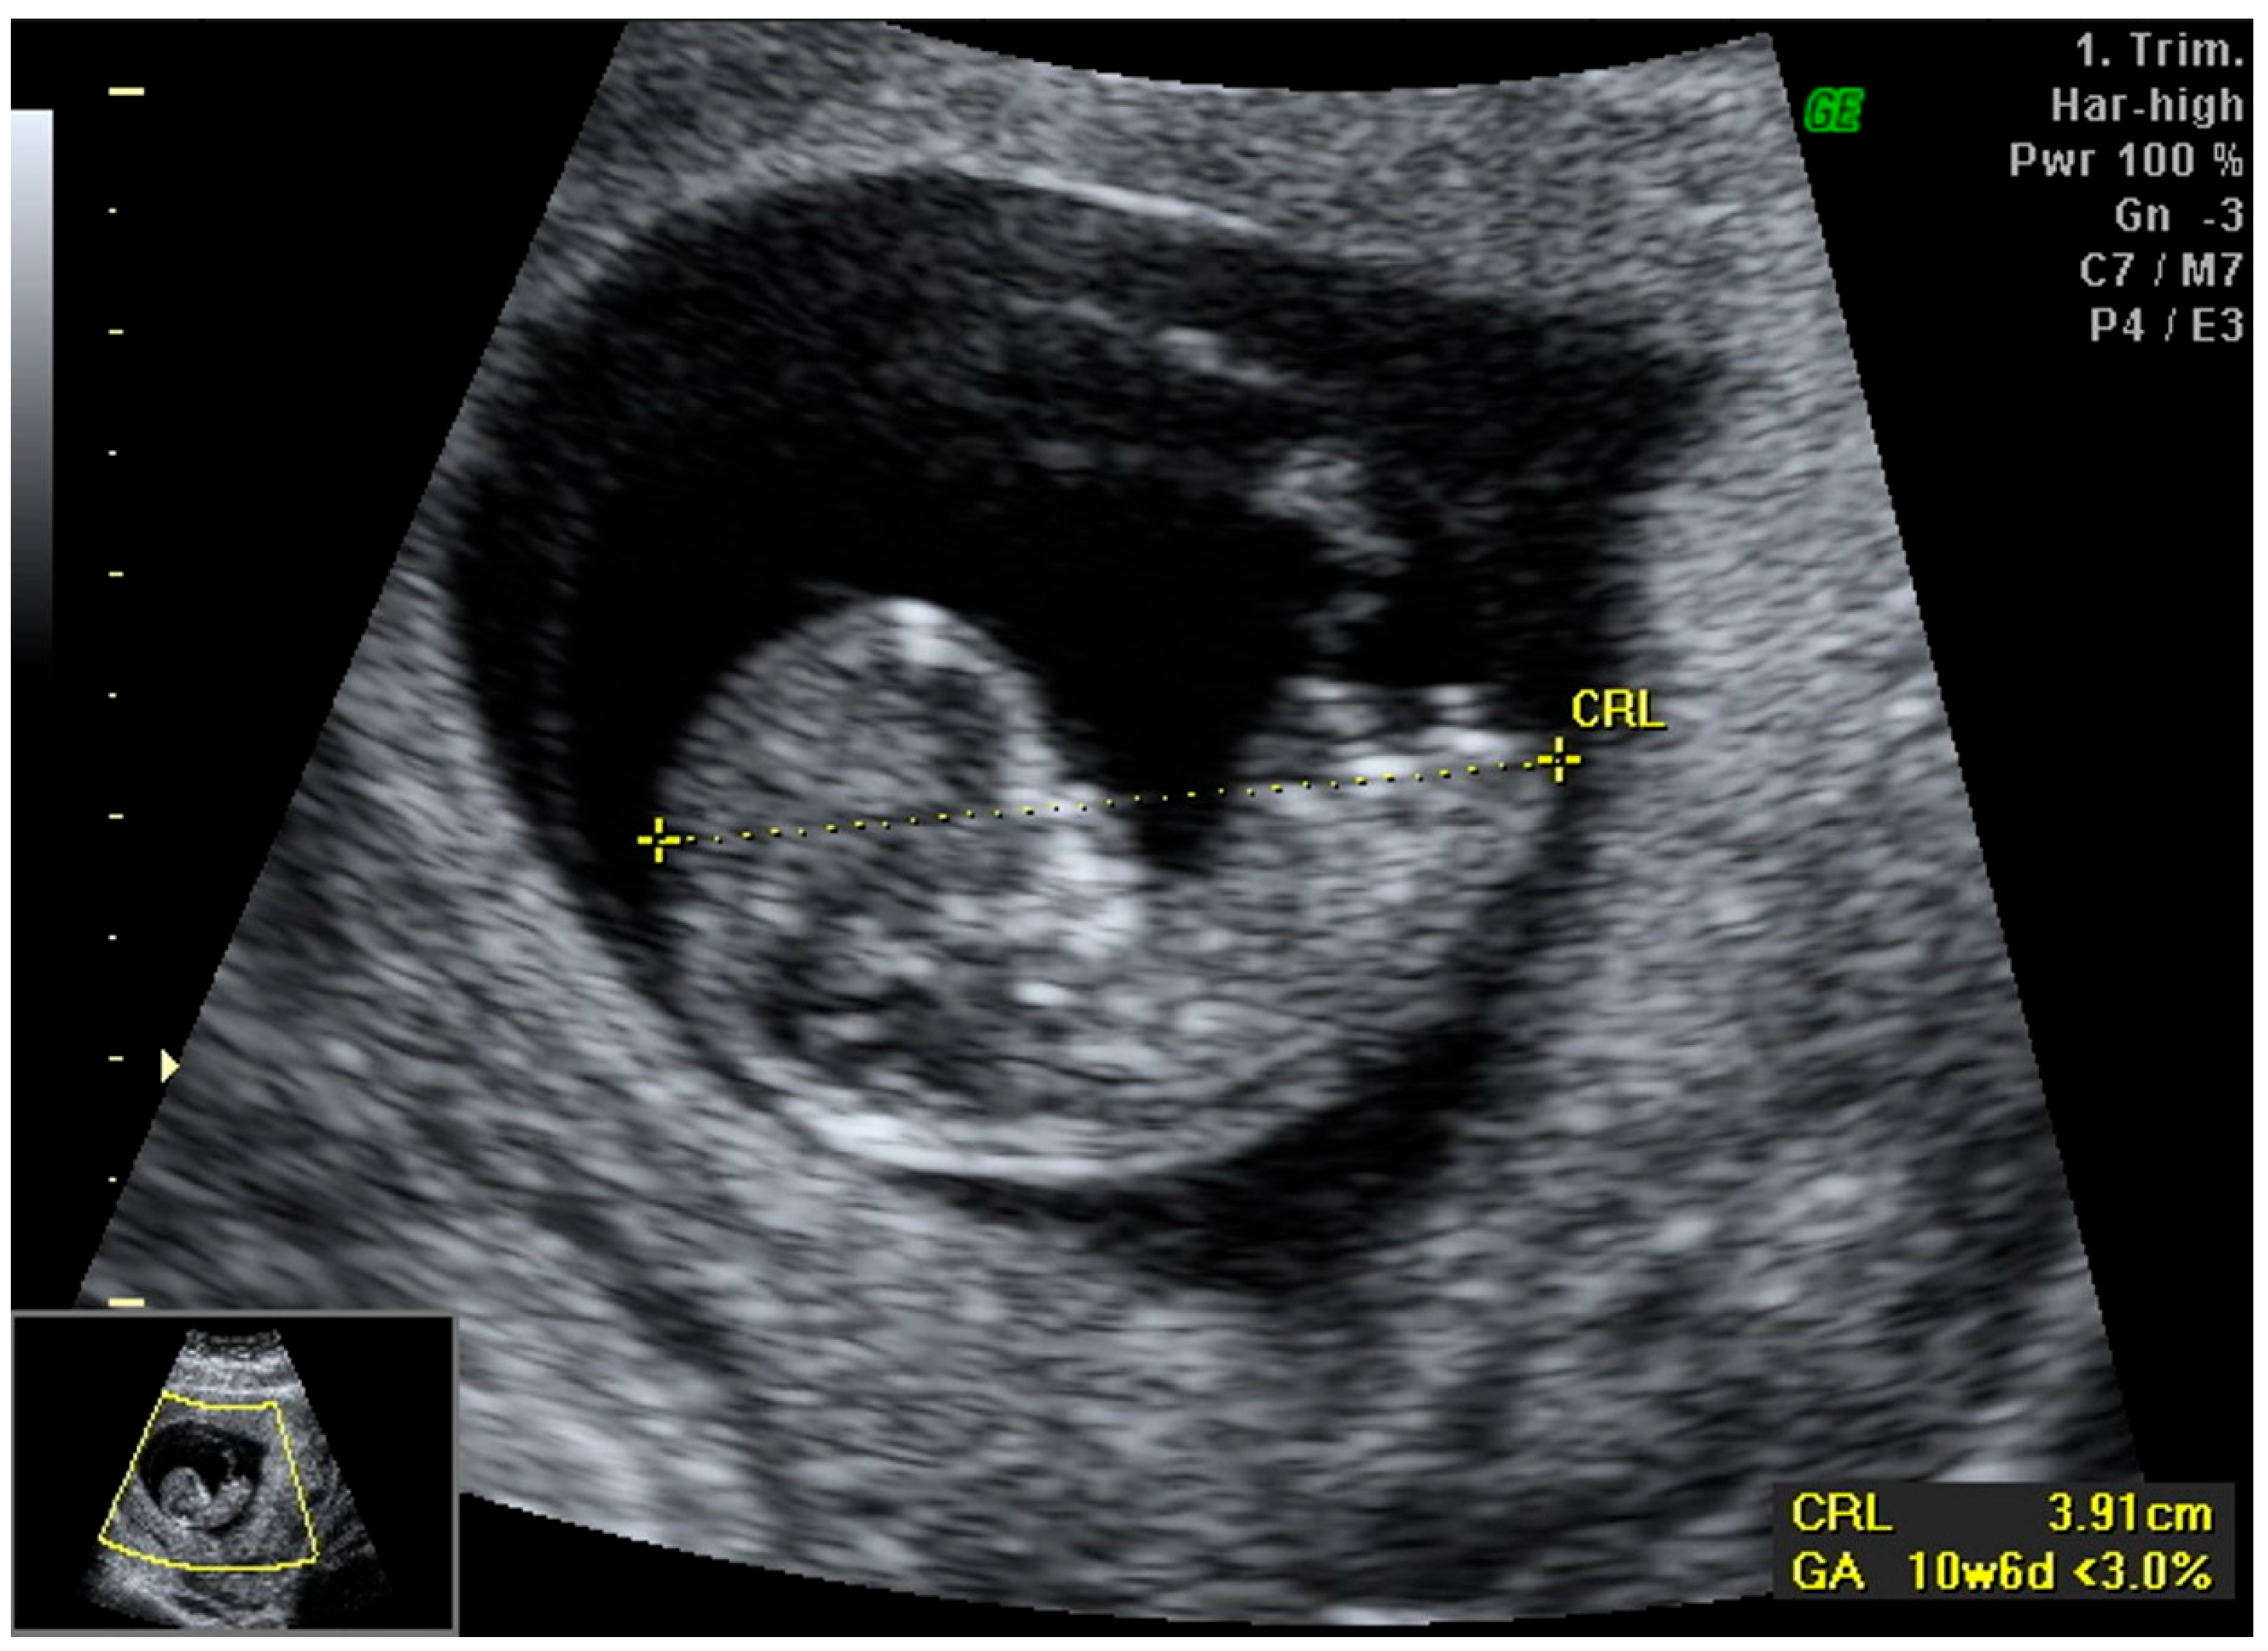

2.1. First-Trimester Findings

- PAPP-A: 0.7 MoM

- Beta-hCG: 0.73 MoM

- Nuchal Translucency (NT): 0.98 mm